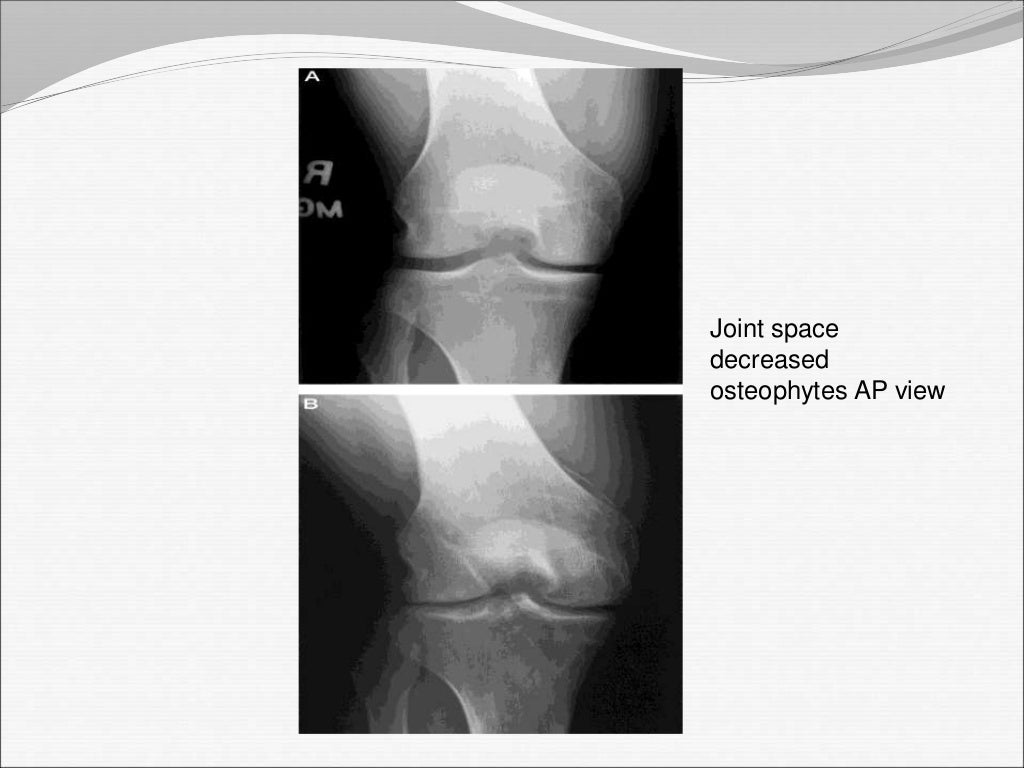

From www.alamy.com

Medical xray knee joint image with arthritis ( Gout , Rheumatoid Septic Arthritis Foot X Ray Septic arthritis is seen on mri as joint effusion, typically with signs of inflammation including pericapsular edema and marginal bone marrow edema at the. A delay in diagnosis and treatment of septic. Septic arthritis (sa) requires urgent treatment to prevent irreversible cartilage destruction, which can occur within hours. Septic arthritis is an emergency that can lead to rapidly progressive, irreversible. Septic Arthritis Foot X Ray.